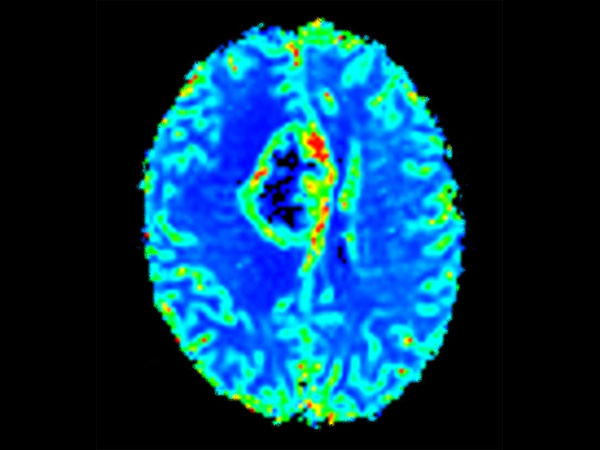

Advanced Neuro imaging - pCASL

Clinique Saint Joseph Imagerie Medicale, Liege, Belgium